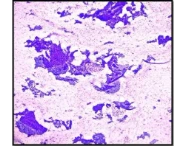

Postpartum Haemorrhage: A Case Series Highlighting Diverse Clinical Profiles and Evolving Management Strategies in a Tertiary Care Setting